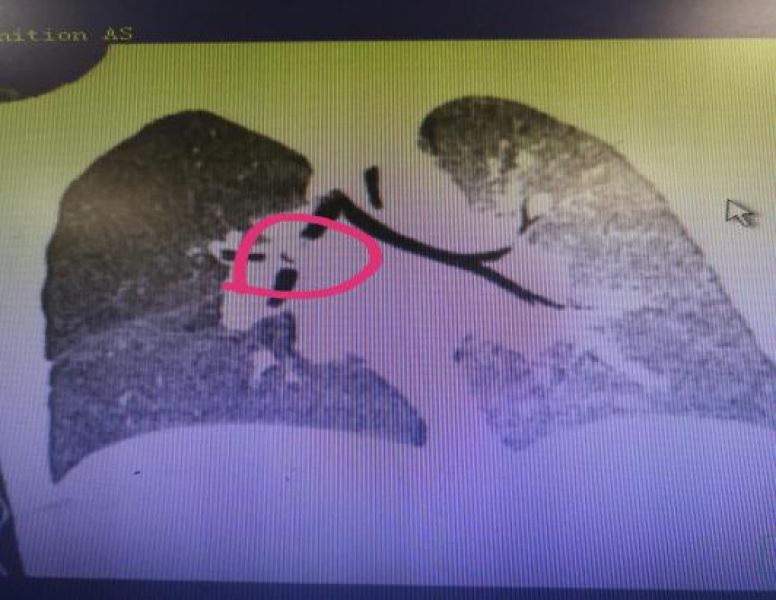

9月6日凌晨,儿一科再次收治一名误吸西瓜籽患儿。该患儿2岁,来自重庆市秀山县,6天前吃西瓜时大哭,随后呛咳,伴喘息,辗转多家医院就诊无果,遂来到我院。于6日中午成功经纤支镜用异物网篮取出一1cm×0.7cm西瓜籽。